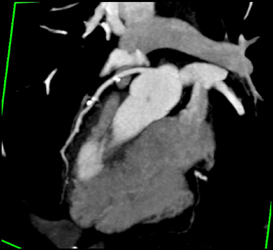

Diagnosis

Normal RCA